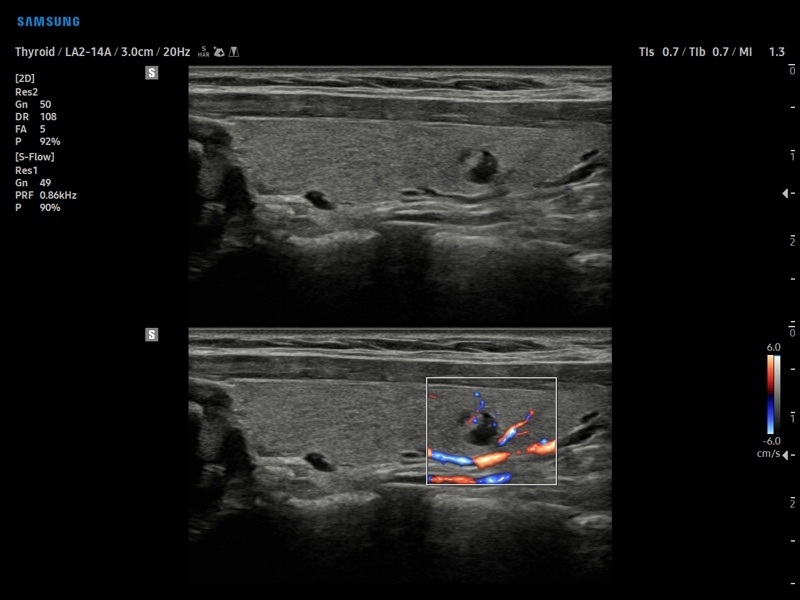

• МодульS-Detect Breast- программа автоматического обнаружения и анализа образований молочной железы у женщин, измерение и классификация по системе BI-RADS.

• МодульS-Detect Thyroid- программа автоматического обнаружения образований и анализа щитовидной железы, измерение и классификация по системе системе TI-RADS.

• Модуль S-Detect Breast - программа автоматического обнаружения и анализа образований молочной железы у женщин, измерение и классификация по системе BI-RADS.

• Модуль S-Detect Thyroid - программа автоматического обнаружения образований и анализа щитовидной железы, измерение и классификация по системе системе TI-RADS.